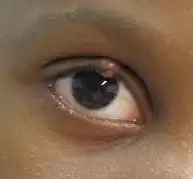

|

| Eyelid affected by a chalazion | |

A chalazion (/kəˈleɪziən/; plural chalazia or chalazions) or meibomian cyst[4] is not a cyst but a granuloma[5] in the eyelid that results from a blocked meibomian gland.[6][7] It typically occurs in the middle of the eyelid, red, and not painful.[2] They tend to develop gradually over a few weeks.[2]

A stye and cellulitis may appear similar.[2] A stye, however, is usually more sudden in onset, painful, and occurs at the edge of the eyelid.[2] Cellulitis is also typically painful.[2]

- Painless swelling on the eyelid

- Eyelid tenderness typically none-to-mild

- Increased tearing

- Heaviness of the eyelid

- Redness of conjunctiva